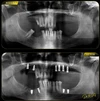

الصور